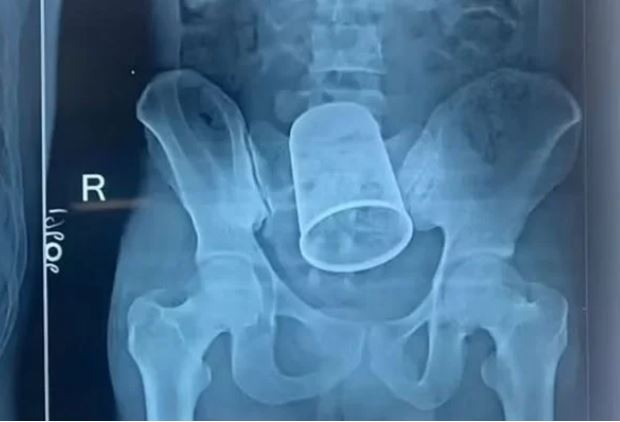

Um jovem de 22 anos precisou passar por uma cirurgia de urgência após ter introduzido um copo de lembrança da festa em que participava na última terça-feira (4), na cidade de Bettiah, na Índia.

Segundo a imprensa local o objeto foi colocado no ânus pelo próprio jovem e tinha cerca de 14 centímetros.

Funcionários do hospital onde o homem foi levado durante a madrugada, gritando de dor e muito sangramento, disseram que foram necessários 11 médicos para fazer a cirurgia no intestino do paciente, cortado para fazer a evacuação.

O homem precisou colocar uma bolsa de colostomia, e segue em observação.